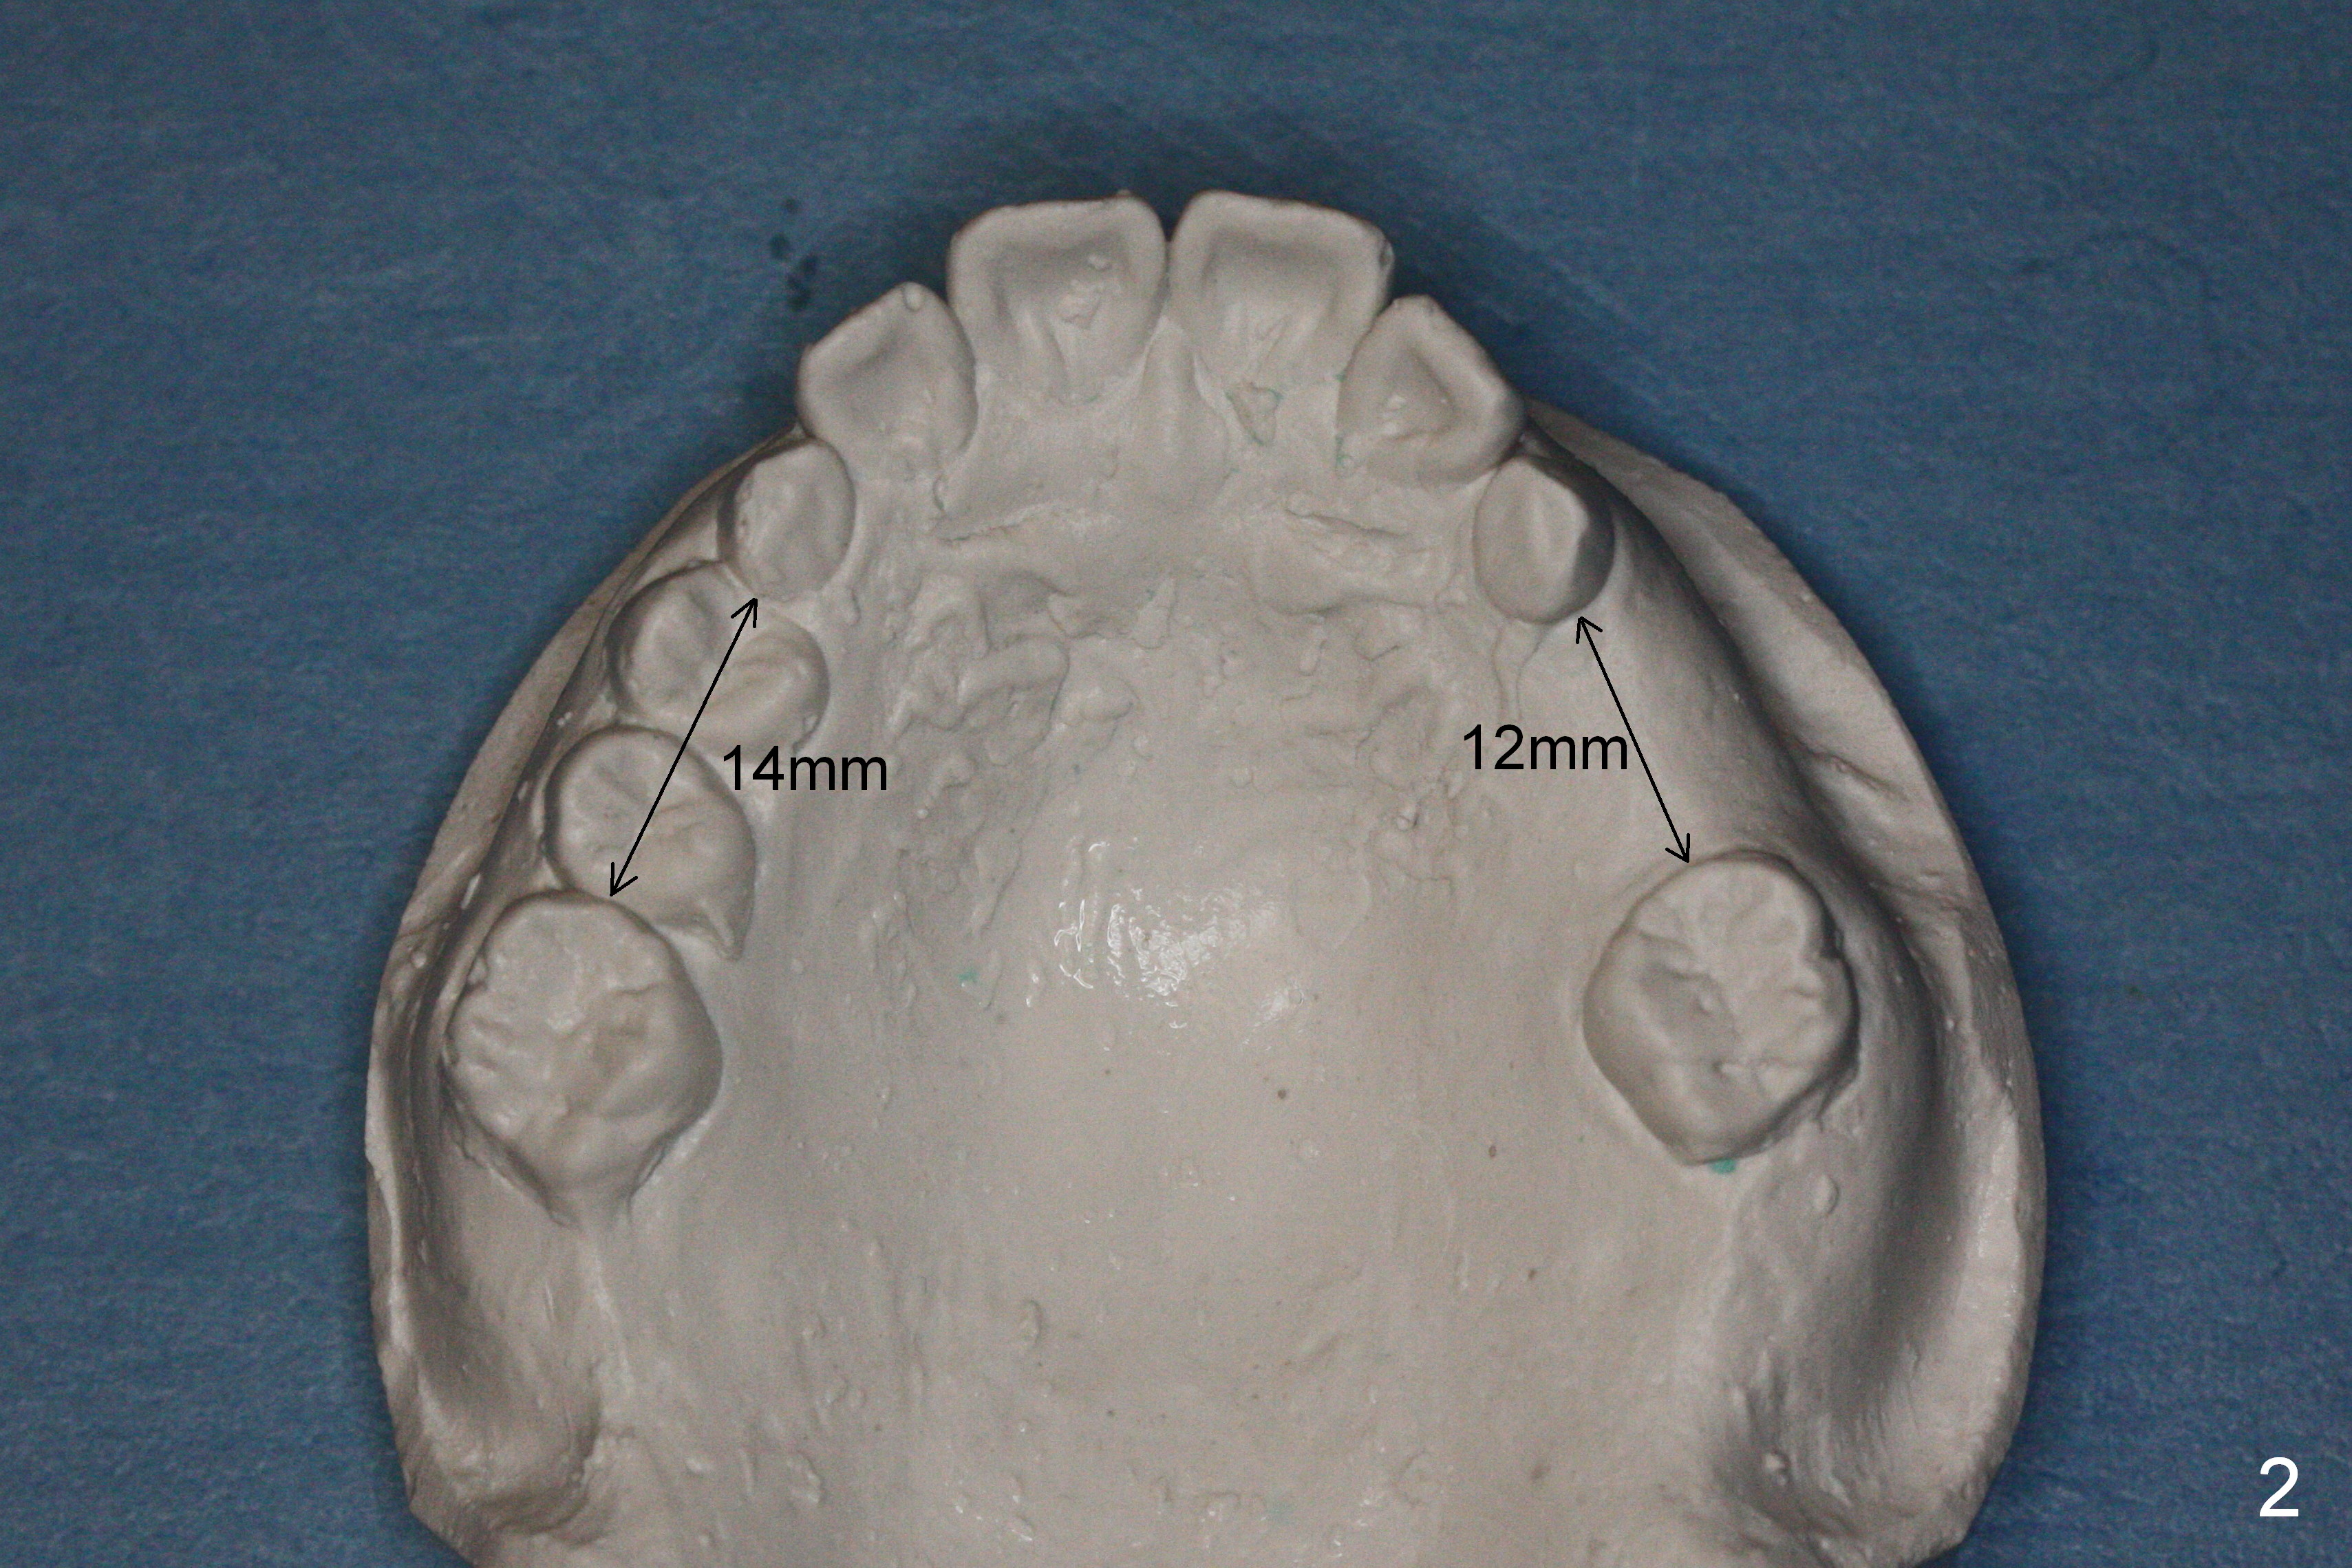

While the upper right bicuspids have erupted, the upper left ones are unerupted and blocked (Fig.2, 6). It appears that the tooth #14 has been mesially shifted (compare Fig.4,5). A space regainer is fabricated (Fig.9). It is not completely seated when cemented, especially at H. The wire holding open coil spring fractures next day. It appears that H is not a good anchor with mobility II. It should be extracted. The mesial anchor will be the tooth #10. If there is sign of anterior tooth protrusion after regainer activation, a mini implant (Tomas, Fig.10 red circle) should be placed in the anterior palate parasagitally and bonded to the cross palatal wire (^).

Panoramic X-ray shows underdevelopment of #20 and 29 tooth buds (Fig.6), which is related to K and T being retained (Fig.3). What should be done for K and T as well as 20 and 29?